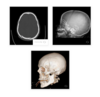

Which dural fold is the arrow pointing to

Tentorium cerebelli

Tentorial notch

Falx cerebelli

A